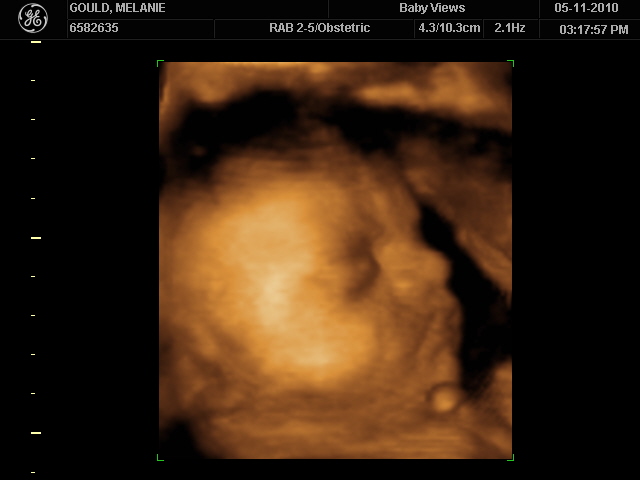

We just loved our ultrasound today - it was such a great experience and I can't say enough good things about Baby Views - Shea is so amazing and does such a great job. It was surreal seeing his little face - what he will look like, minus all the fluid swimming around him - ha! He is just precious - a doll - of course he is my son, so I am definitely going to think he is a cutie. But don't take my word for it - see for yourself!

Here is the money shot - he showed us his sweet face for a while, and then he was tired of that and started playing with his hands and feet. He pretty much stayed in this position for 10 minutes of the ultrasound - waving his hands all in his face and pulling his feet/toes with his hands - too funny. He is definitely a showoff - we tried to get him to pull his hands away so we could see his face more - I even rolled over twice onto my side, but no progress. He was perfectly happy with the position he was in - though it looked quite uncomfortable to us!

He even scrunched his forehead at one point and it looked like he was getting mad - it was too stinkin cute!